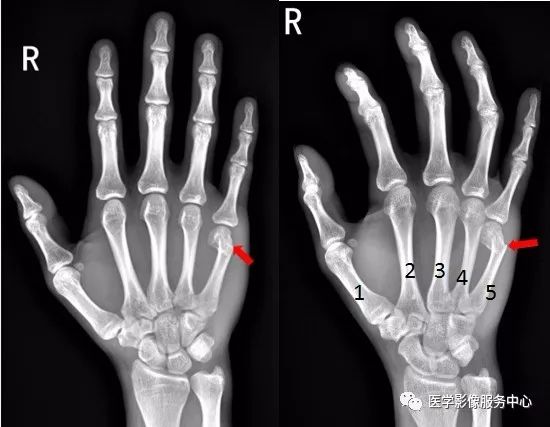

右手第五掌骨远端骨皮质不连续,骨折端移位、成角。右手第五掌骨骨折(1-5. 第1-5掌骨)

图片

右手第四掌骨中段、第五掌骨基底部见横行骨折透亮线,骨折端对位对线尚可。第四、第五掌骨骨折。